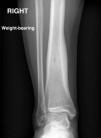

An X-ray was ordered (Fig. 1), which revealed a punctiform cortical lesion in the right tibia with a perilesional osteosclerotic reaction. Computed tomography and magnetic resonance imaging (Figs. 2 and 3) revealed an oval lytic lesion measuring 5 × 8 mm in the posteroinferior cortex of the tibia with reactive sclerosis, consistent with osteoid osteoma. In light of this suspected diagnosis, he was referred to traumatology and is awaiting treatment with radiofrequency ablation.1